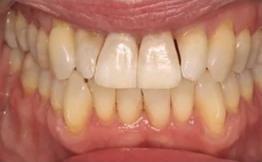

Soft tissue analysis: Beyond tooth health there are a number of serious oral health problems that can affect the oral mucosa as well as the tongue. The field of dermatology has spearheaded the use of natural light photography for the detection of skin lesions, and there is real potential in using it in oral care for the detection of mucosal lesions, tongue abnormalities, oral cancers or gingival inflammation and recession.

Connected personal devices: Clinicians and researchers in dentistry have started to use natural-light or smartphone photography in the detection and monitoring of mucosal lesions, tongue abnormalities, and oral cancers. In clinical practice, the images are still only used for documentation and referral. In research, AI models trained on these images are demonstrating promising performance for automated screening, particularly in low-resource or telehealth contexts.